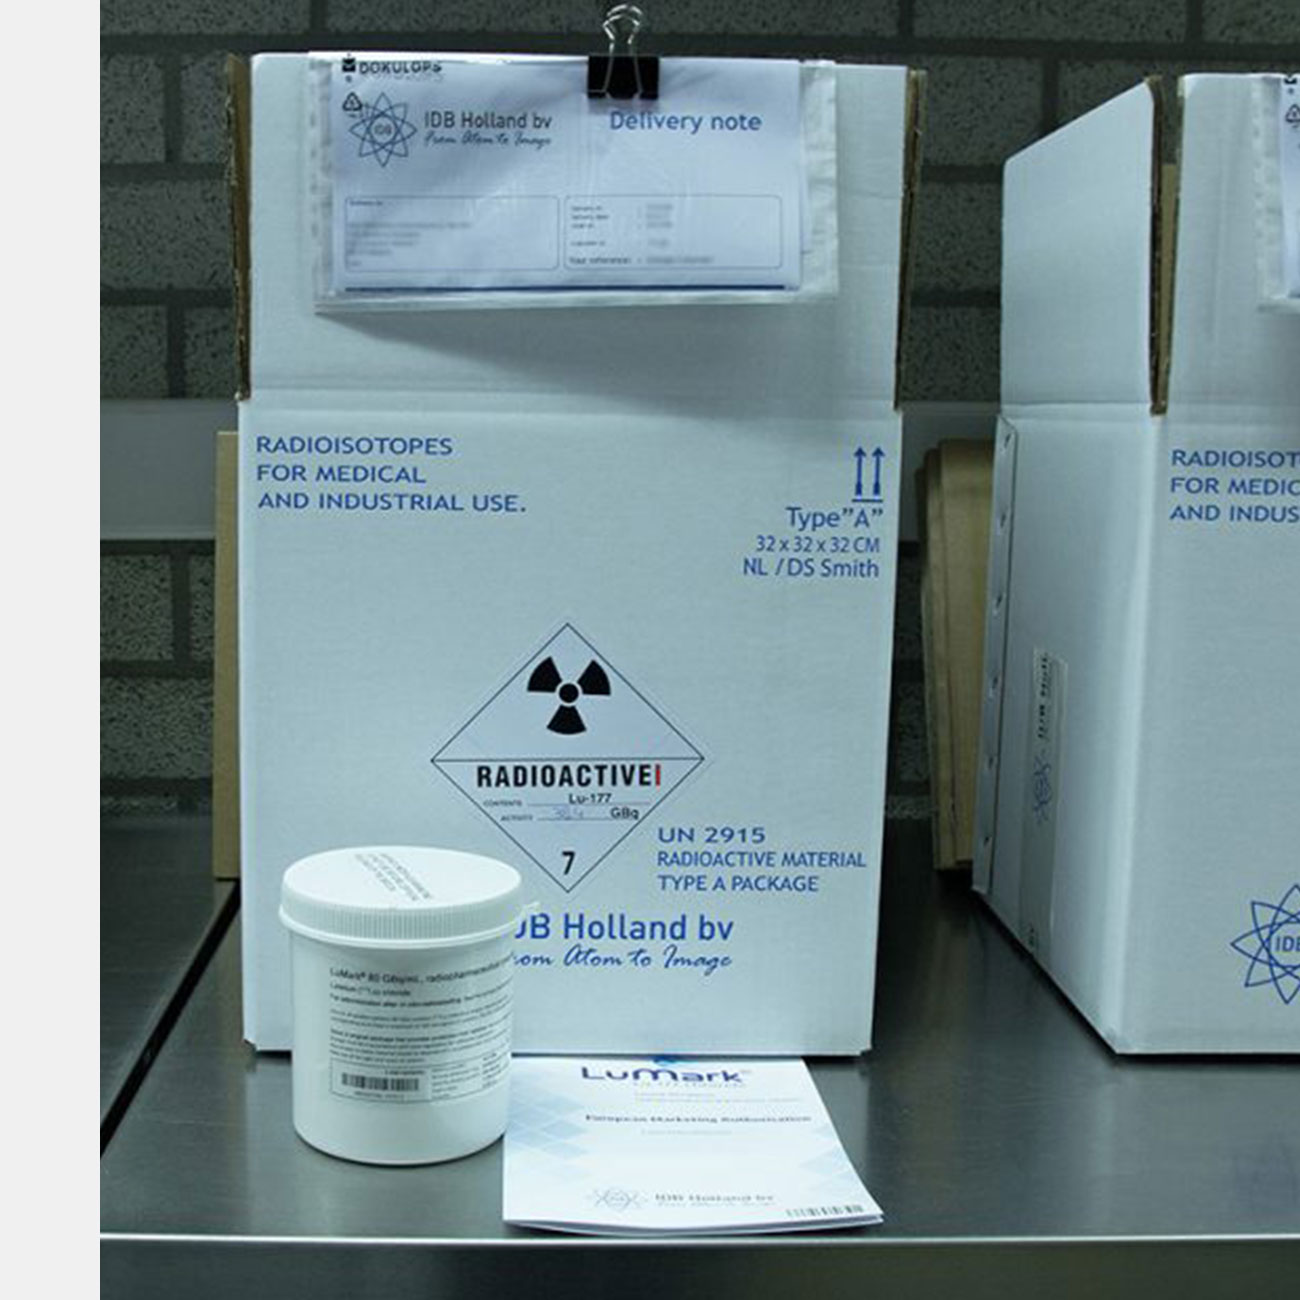

Российские ученые разработали новый метод получения лютеция-177 для лечения онкологических заболеваний. Предполагается, что он может стать альтернативой технологии наработки изотопов в исследовательских ядерных реакторах. Об этом пишет ТАСС со ссылкой на сообщение заведующего лабораторией радионуклидов и радиофармпрепаратов НИЦ «Курчатовский институт» Рамиза Алиева.